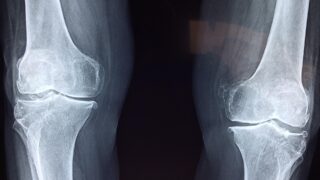

膝関節の骨壊死に対するUKAの治療成績に対する治療成績についての論文の紹介です。

Reliable outcomes and survivorship of unicompartmental knee arthroplasty for isolated compartment osteonecrosis 」

Bone Joint J 2018;100-B:450–4

膝の骨壊死に対しては早期の病期に対しては保存的加療(足底板や免荷)や関節鏡を用いた手術により関節温存が行われる。しかし、より病期の進行した骨壊死に対しては人工関節手術が考慮される。片側の膝の骨壊死は、片側の障害であり・軟部組織や靱帯に問題が無いことなどからUKAの良い適応であると考えられ、手術が行われてきた。

しかしこれまでの報告では、片側の(内側or外側)骨壊死に対するU K Aの結果に関する報告は多くない。また中長期の結果やT K Aへの再手術の割合に関する報告は少ない。

この研究の目的は、骨壊死に対するU K Aの生存期間(1revision,reoperation にならずに経過した期間)、失敗例の危険因子、臨床成績、合併症を分析することである。